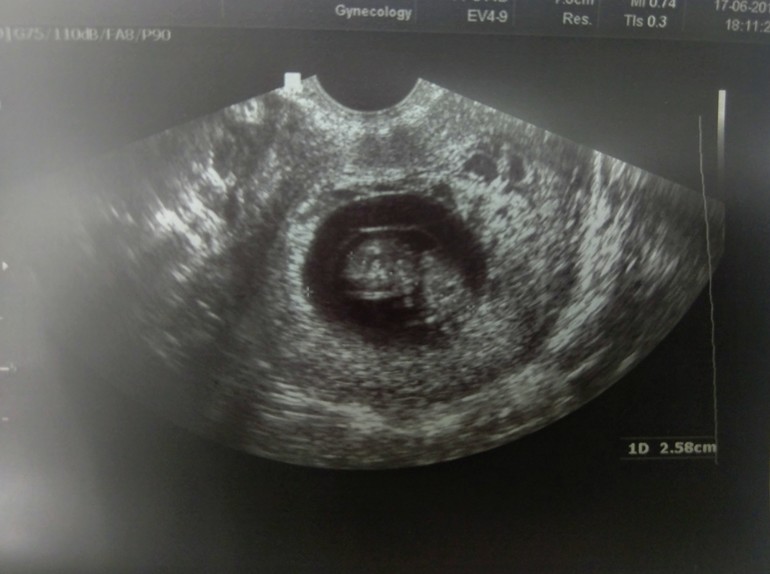

А ещё сравнила на последнем узи качество аппаратов, на одном было еле видно в ЖК даже сама врач сказала, что аппаратура тут ужас, а у своего врача в платной видела как машет руками и шевелится. В 9 недель уже видно мини ладошку. А в жк просто белое пятно)))

У нас с вами одинаковый срок у меня 19 тоже 8+6) и тоже 22мм. Меня на скрининг ещё не записали, жду звонка врача, назвала КТР они сами рассчитывают когда надо на скрининг. Слышала что 20 недель важнее скирининг и расслабится все равно вряд ли получится. Но очень хочется!